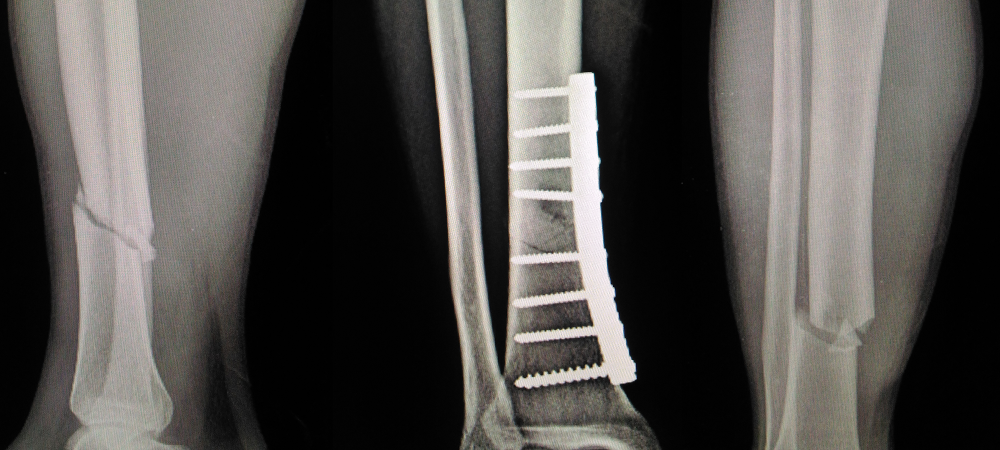

Mini fragment systems are specifically engineered for the stabilization and fixation of small bones and fractures, particularly in areas like the hand, wrist, foot, and ankle. These systems include a range of small plates, screws, and instruments tailored for delicate bone structures. The miniaturization of these components does not compromise their strength or functionality; rather, it provides surgeons with the ability to perform precise, targeted repairs that were once deemed highly challenging.

The versatility of mini fragment systems allows for their application across a wide spectrum of small bone surgeries. From complex fractures in the fingers and toes to reconstructive procedures in the wrist and ankle, these systems facilitate optimal alignment and stabilization of bone fragments. Their use is crucial not only in trauma cases but also in orthopedic corrections and reconstructive surgeries, where the precise alignment of small bones is critical for the restoration of function.

Mini fragment systems offer several advantages over traditional fixation methods. The precision and size of the components are ideally suited for the small and often complex anatomical structures they are designed to repair. This leads to less invasive surgeries, reduced soft tissue disruption, and consequently, faster recovery times for patients. Moreover, the specialized design of these systems ensures a more secure fixation, minimizing the risk of hardware migration and promoting better healing outcomes.